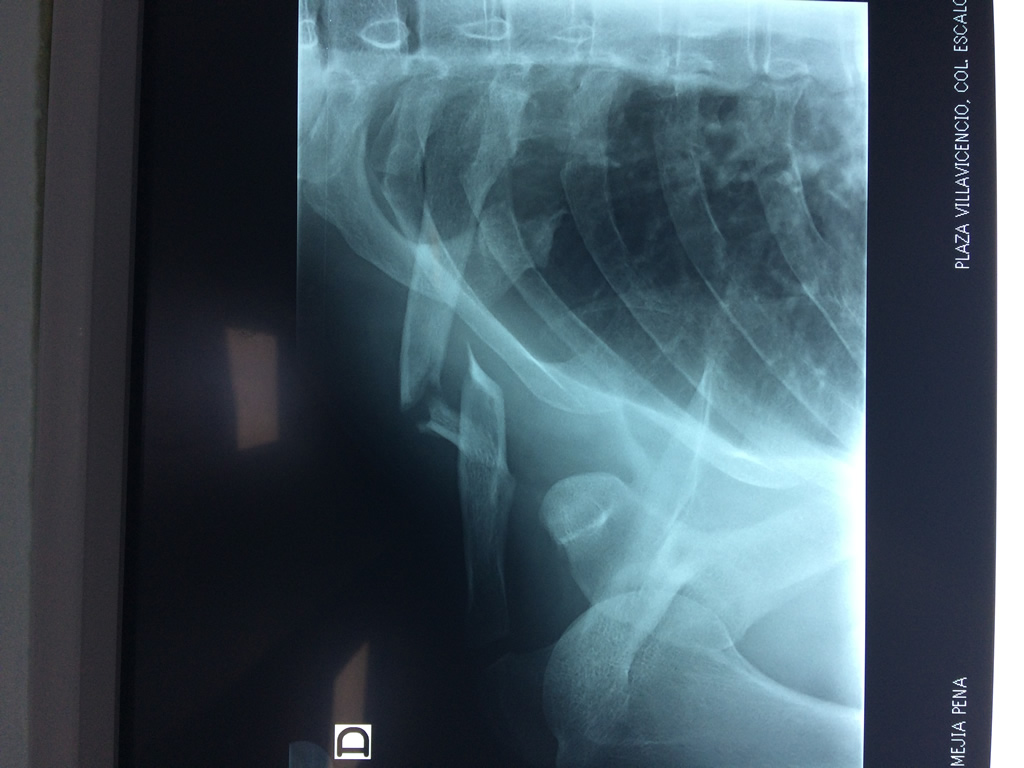

Húmero - Clavícula

La clavícula es un hueso largo, con forma de "S" itálica, situado en la parte anterosuperior del tórax. Junto con la escápula forman la cintura escapular. Se puede palpar por toda su longitud y se extiende del esternón al acromion de la escápula, siguiendo una dirección oblicua lateral y posterior.